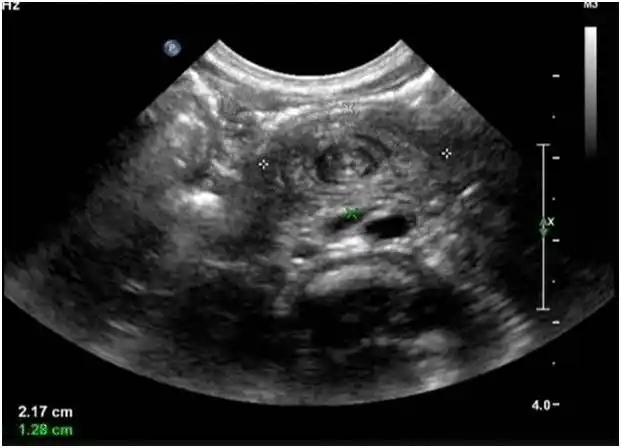

小儿巨大肠系膜淋巴管瘤并肠扭转肠梗阻1例

「漩涡征」:超声诊断小肠扭转的线索